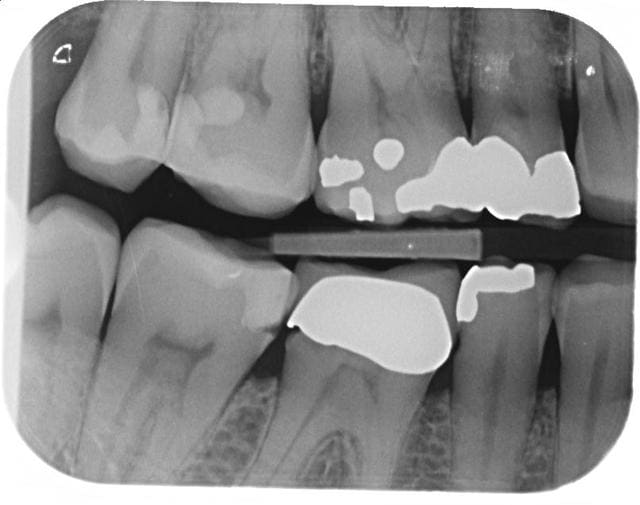

Voici un cas. Patiente 60 ans, RAS anamnèse.

Carie distale sous 47 couronnée et traitée.

Pas de douleurs, aucun signe clinique.

La carie a l'air basse, je ne suis pas sur de la solidité restante des racines après dépose.

Si tu ne fais rien on peut te reprocher une perte de chance d'après la radio la racine a l'aire conservable.

Avec la radio tu es couvert pour déposer la couronne.

Plus bonus si tu dépose la couronne de 47 tu pourras probablement soigner le début de carie en distal de 46 sans déposer la couronne.

Refaire la 47. En profiter pour vérifier la limite distale pas nette de la 46, et probablement refaire 46 dans la foulée.

déposer la 47 ne sera pas difficile, vue l'absence de tenon. nettoie bien dessous et recouronner.

La théorie dirait que oui, il y a perte d'étanchéité coronaire depuis longtemps, et la conicité du traitement semble assez faible.